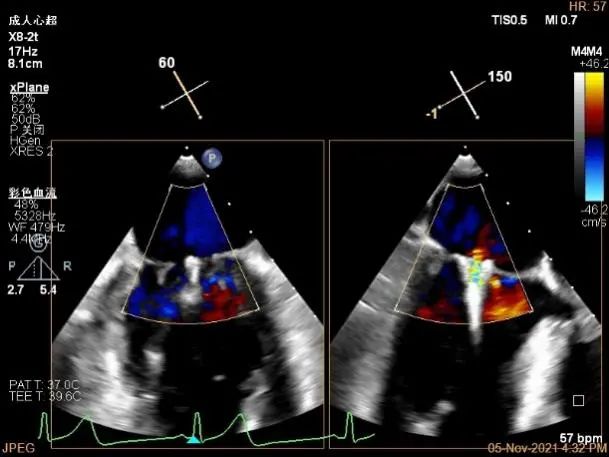

3D MV View:A2/A1区脱垂

3D-color MV view:血流主要来源于A2区,少部分来源于A1区

TEE Bicom view:主要脱垂区域为2区

Color-view:返流束主要来源于2区脱垂

A1P1区后叶发育短小,约5.3mm

A2P2区前后叶长度可,为主要脱垂区域,进而制定手术策略: 2区一个长夹子解决脱垂主要病变区域